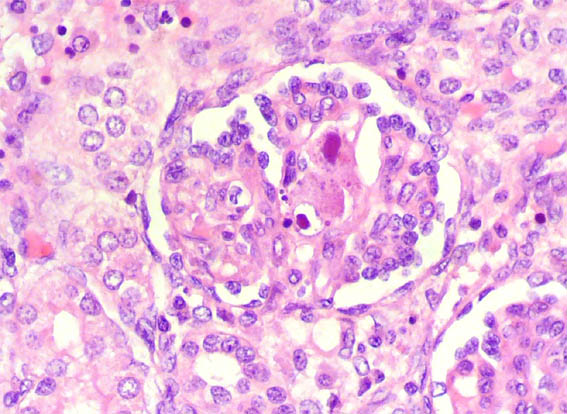

En ambos riñones fetales se observa lo mostrado en las siguientes imágenes.

Figura 3.

H&E, X400.